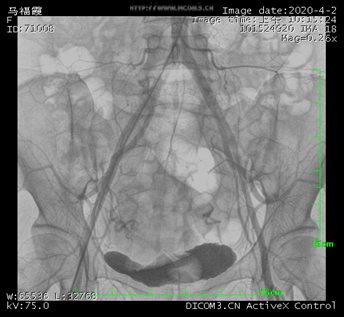

髂總動脈造影

數字減影血管造影機((Digital subtraction angiography,DSA),一般由X線發生裝置、數字成像系統、機械系統、計算機控制系統、圖像處理系統以及輔助系統等組成。DSA是通過電子計算機進行輔助成像的血管造影方法。它是應用計算機程序進行兩次成像完成的,在注入造影劑之前,首先進行第一次成像,并用計算機將圖像轉換成數字信號儲存起來,注入造影劑后再次成像并轉換成數字信號,兩次數字相減,消除相同的信號,得到一個只有造影劑的血管圖像,這種圖像較以往所用的常規血管造影劑所顯示的圖像更清晰、更直觀,一些精細的血管結構亦能顯示出來。

簡單來說就是將造影劑注入需要檢查的血管中,使血管顯露原形。然后通過系統處理,使血管顯示更加清晰,便于醫生診斷或進行手術,這也是為什么DSA被稱為“血管機”的原因。DSA的臨床使用范圍廣泛,適用于心、腦、外周及各部位血管、腫瘤、泌尿、呼吸道以及其它消化道在內的各科室臨床診斷和微創介入治療。